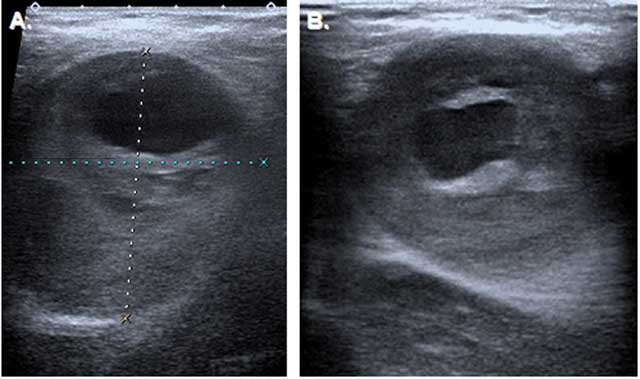

Figure 2

Ultrasonography of the axillary masses. (A) Transverse section show 67 × 45 mm partially thrombosed aneurysm on the right, (B) 40 × 45 mm partially thrombosed aneurysm on the left.